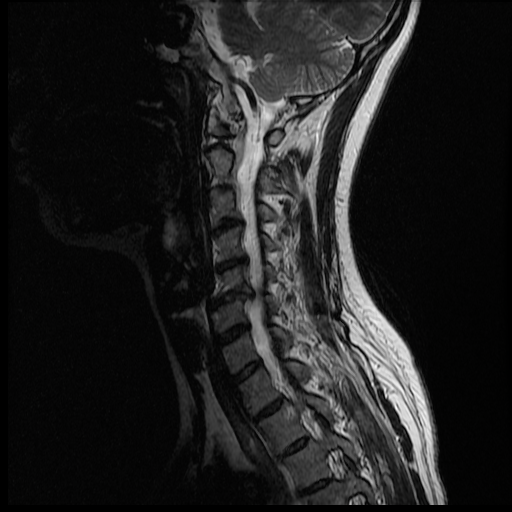

I'm waiting anxiously for Monday morning, but my husband has been pouring over the MRI images most of the night and even this morning. He's not a doctor, but it seems I may have a herniated disc. I hope this is the only thing going on.... The thing is we don't know if this is C6/C7 (where the lesion was seen), or C5/C6. Here are some of the pictures that show that the disc may be bulging/herniated.

Hopefully the experts come to the same conclusion, and that there isn't anything else... only Monday will tell.